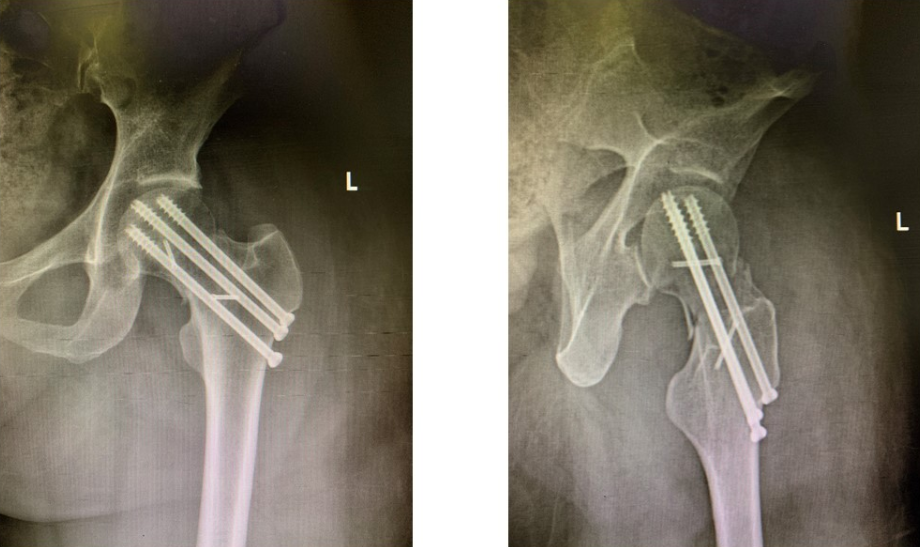

术后,骨科启动MDT机制,在手术室、麻醉科的密切配合下,由罗令教授带领的团队为患者成功开展了显微镜下创新性旋髂深血管蒂髂骨瓣移植联合股骨颈空心钉内固定术。术后,护士长张文秀带领团队指导患者进行康复锻炼,现已顺利出院。

罗令教授介绍,对于年轻的股骨颈骨折(Pauwells III型,Garden IV型)患者,股骨头预期坏死率高,带旋髂深血管蒂髂骨瓣移植预防股骨头坏死是一种很有效的治疗方法,但经典手术方式存在创伤大、血管已受卡压从而影响髂骨瓣存活等缺点。湘雅三医院创伤骨科对原有术式进行了多项改良,新术式降低了移植血管受压可能性,移植后的髂骨瓣成活率更高,完整地保留了腹股沟结构与功能,还保留了髂骨的外形,供区损伤更小,更符合目前微创、美学的理念。5年来,创伤骨科已成功为20名股骨颈骨折中青年患者开展了保髋手术,股骨头坏死率由40%降低至10%。